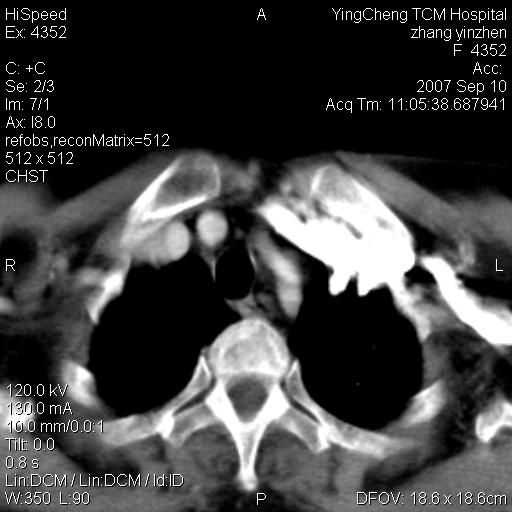

以下是引用卜一在2007-9-18 14:41:00的发言:[br]右肺肿块:毛刺+胸膜凹陷征+供血血管+浅分叶+强化。支持:周围性肺癌 !另:左侧甲状腺腺瘤!

以下是引用夏季在2007-9-18 11:00:00的发言:[br]1。右肺肿块,周围有短毛刺,肺门侧有血管与其相连,胸壁侧有胸膜凹陷征,考虑周围性肺癌 2。左侧甲状腺软组织肿块,内有高密度钙化灶,考虑左侧甲状腺腺瘤。